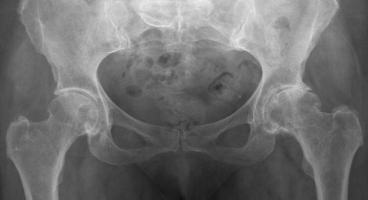

Коксартроз — это разновидность артрита, которая представляет собой тяжелое дегенеративно-дистрофическое заболевание структурных элементов тазобедренного сустава, характеризующееся воспалительным поражением, которое приводит к его деформации (Рис. 1). В основе заболевания лежит процесс дезадаптивной регенерации тканей сустава, вызванный воздействием вредных факторов. Поражаются все компоненты тазобедренного сустава: гиалиновый хрящ, субхондральная кость, синовиальная оболочка, связки, капсулы, а также периартикулярные мышцы [5]. Может быть как односторонним, так и двусторонним. Данное заболевание трудно поддается консервативному и оперативному лечению. Возникает коксартроз в результате взаимодействия генетических, возрастных, гормональных и средовых факторов, но нередко встречаются случаи неясной этиологии. В зависимости от источника болезни выделяют первичный (идиопатический) и вторичный (механоиндуцированный) коксартроз.

Рис. 1. Коксартроз 1 стадии [2]